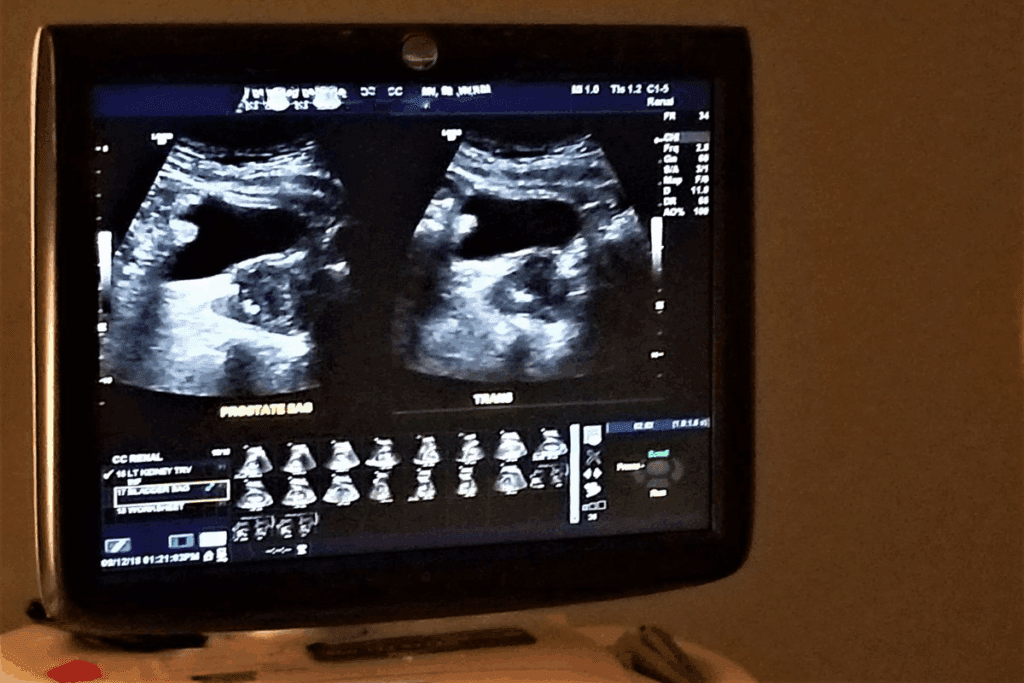

Types of Pelvic Ultrasound Procedures

Transabdominal Ultrasound Overview

For a transabdominal ultrasound, a transducer is placed on your belly. It gives a wide view of the pelvic area. You need a full bladder for the best pictures.

Transvaginal Ultrasound Explained

Transvaginal ultrasound uses a special transducer in the vagina. It gives clearer pictures of the reproductive organs. This is great for detailed checks.

When Both Methods Are Used Together

Doctors often use both transabdominal and transvaginal ultrasounds together. This way, they get a full view and detailed images. It’s a thorough way to check the pelvic area.